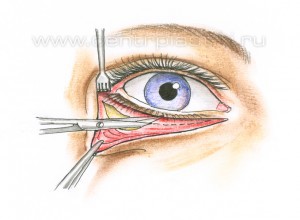

Рис. 5 Подтяжка средней зоны лица обычно выполняется под наркозом. Среднее время операции 1,5-2 часа. Разрез кожи и мышцы выполняется под ресничным краем нижнего века. Рис. 6.

Рис. 9 Через боковую часть разреза выполняется отделение надкостницы от костей в проекции средней зоны лица вниз до крыла носа, обычно для этого используются эндоскопические инструменты. Рис. 11 Мобилизованные ткани прошиваются в верхненаружном углу и фиксируются к надкостнице выше наружного угла глаза. Рис. 12 Выполняется миопексия (фиксация мышцы окружающей глаз) Рис. 13 и кантопексия (фиксация наружного угла глаза), Рис. 14 затем удаляется избыток кожи Рис. 15. Этим достигается правильное положение глазной щели и удается добиться разглаживания мелких морщин. В конце операции кожная рана зашивается косметичным внутрикожным швом.